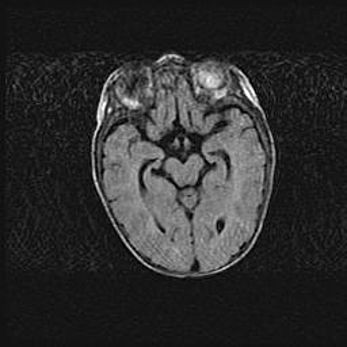

Множественные кисты обоих полушарий головного мозга, наибольшая из них в правой затылочной области. Ассиметричная атрофическая гидроцефалия.

Возраст: 7 месяцев

Вес: 5660 г

Пол: мужской

Окружность головы: 41,5 см

Срок гестации: 28-29 недель

Кисты головного мозга развиваются в результате многоочаговых некрозов вещества мозга и возникают вследствие перенесенной перинатальной инфекции, менингитов, энцефалитов, асфиксии, родовой травмы, расстройств мозгового кровообращения различного генеза. Образованию кист в веществе головного мозга плодов и новорожденных способствуют такие факторы, как высокое содержание в нем воды, недостаточная (или отсутствие) миелинизация и слабая астроглиальная реакция на повреждение.

Кисты могут сочетаться с гидроцефалией и другими поражениями головного мозга.